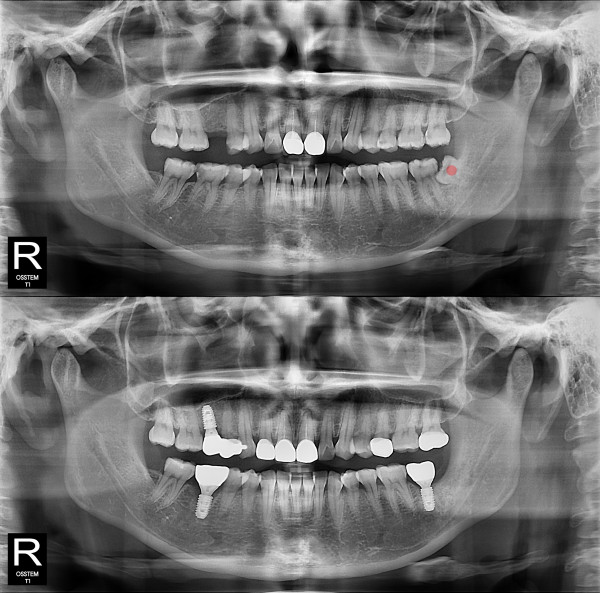

智齿拔除 部分埋伏智齿